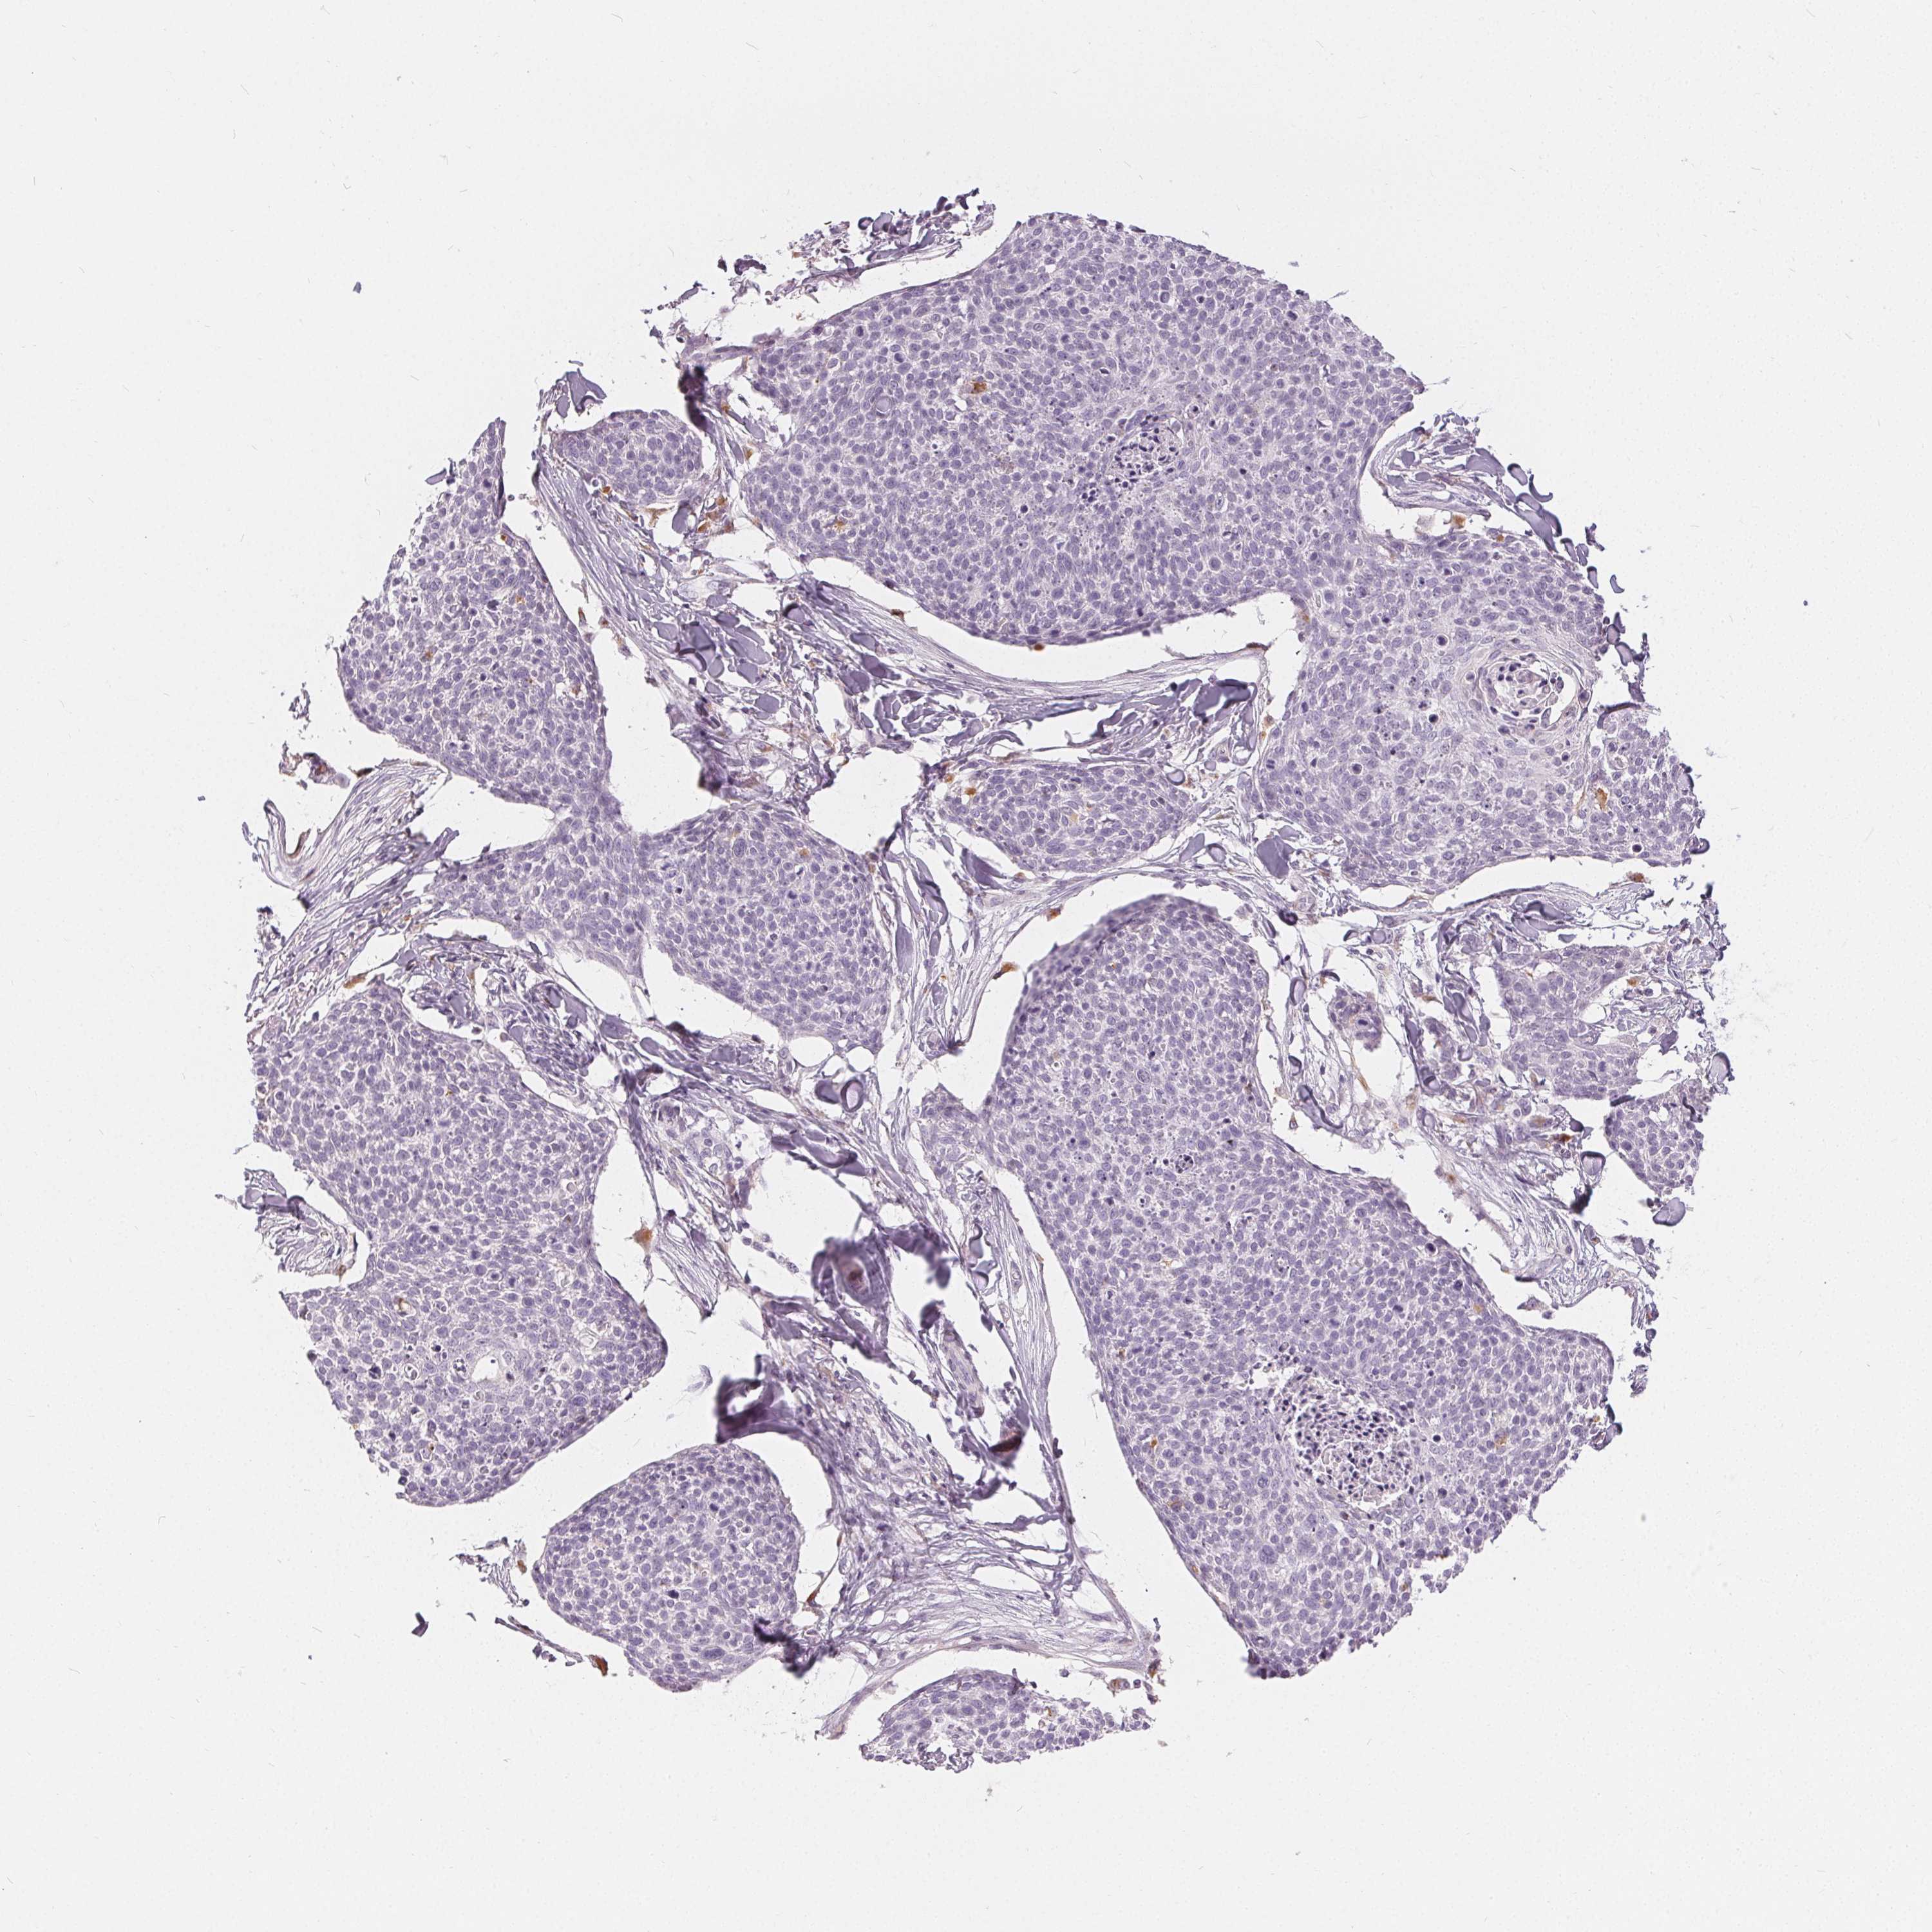

Basal cell and squamous cell cancer

SKIN CANCER - Protein expressioni

A mouse-over function shows sample information and annotation data. Click on an image to view it in a full screen mode. Samples can be filtered based on level of antibody staining by selecting one or several of the following categories: high, medium, low and not detected. The assay and annotation is described here.

Antibody stainingi

Antibody staining in the annotated cell types in the current human tissue is reported as not detected, low, medium, or high, based on conventional immunohistochemistry profiling in selected tissues. This score is based on the combination of the staining intensity and fraction of stained cells.

Each image is clickable and will lead to virtual microscopy that enables deeper exploration of all samples and also displays staining intensity scores, fraction scores and subcellular localization as well as patient and tissue information for each sample.

Antibody HPA030180

Antibody CAB018632

Staining

High

Medium

Low

Not detected

Intensity

Strong

Moderate

Weak

Negative

Quantity

>75%

75%-25%

<25%

None

Location

Nuclear

Cytoplasmic/membranous

Cytoplasmic/membranous,nuclear

Basal cell carcinoma

Squamous cell carcinoma, NOS